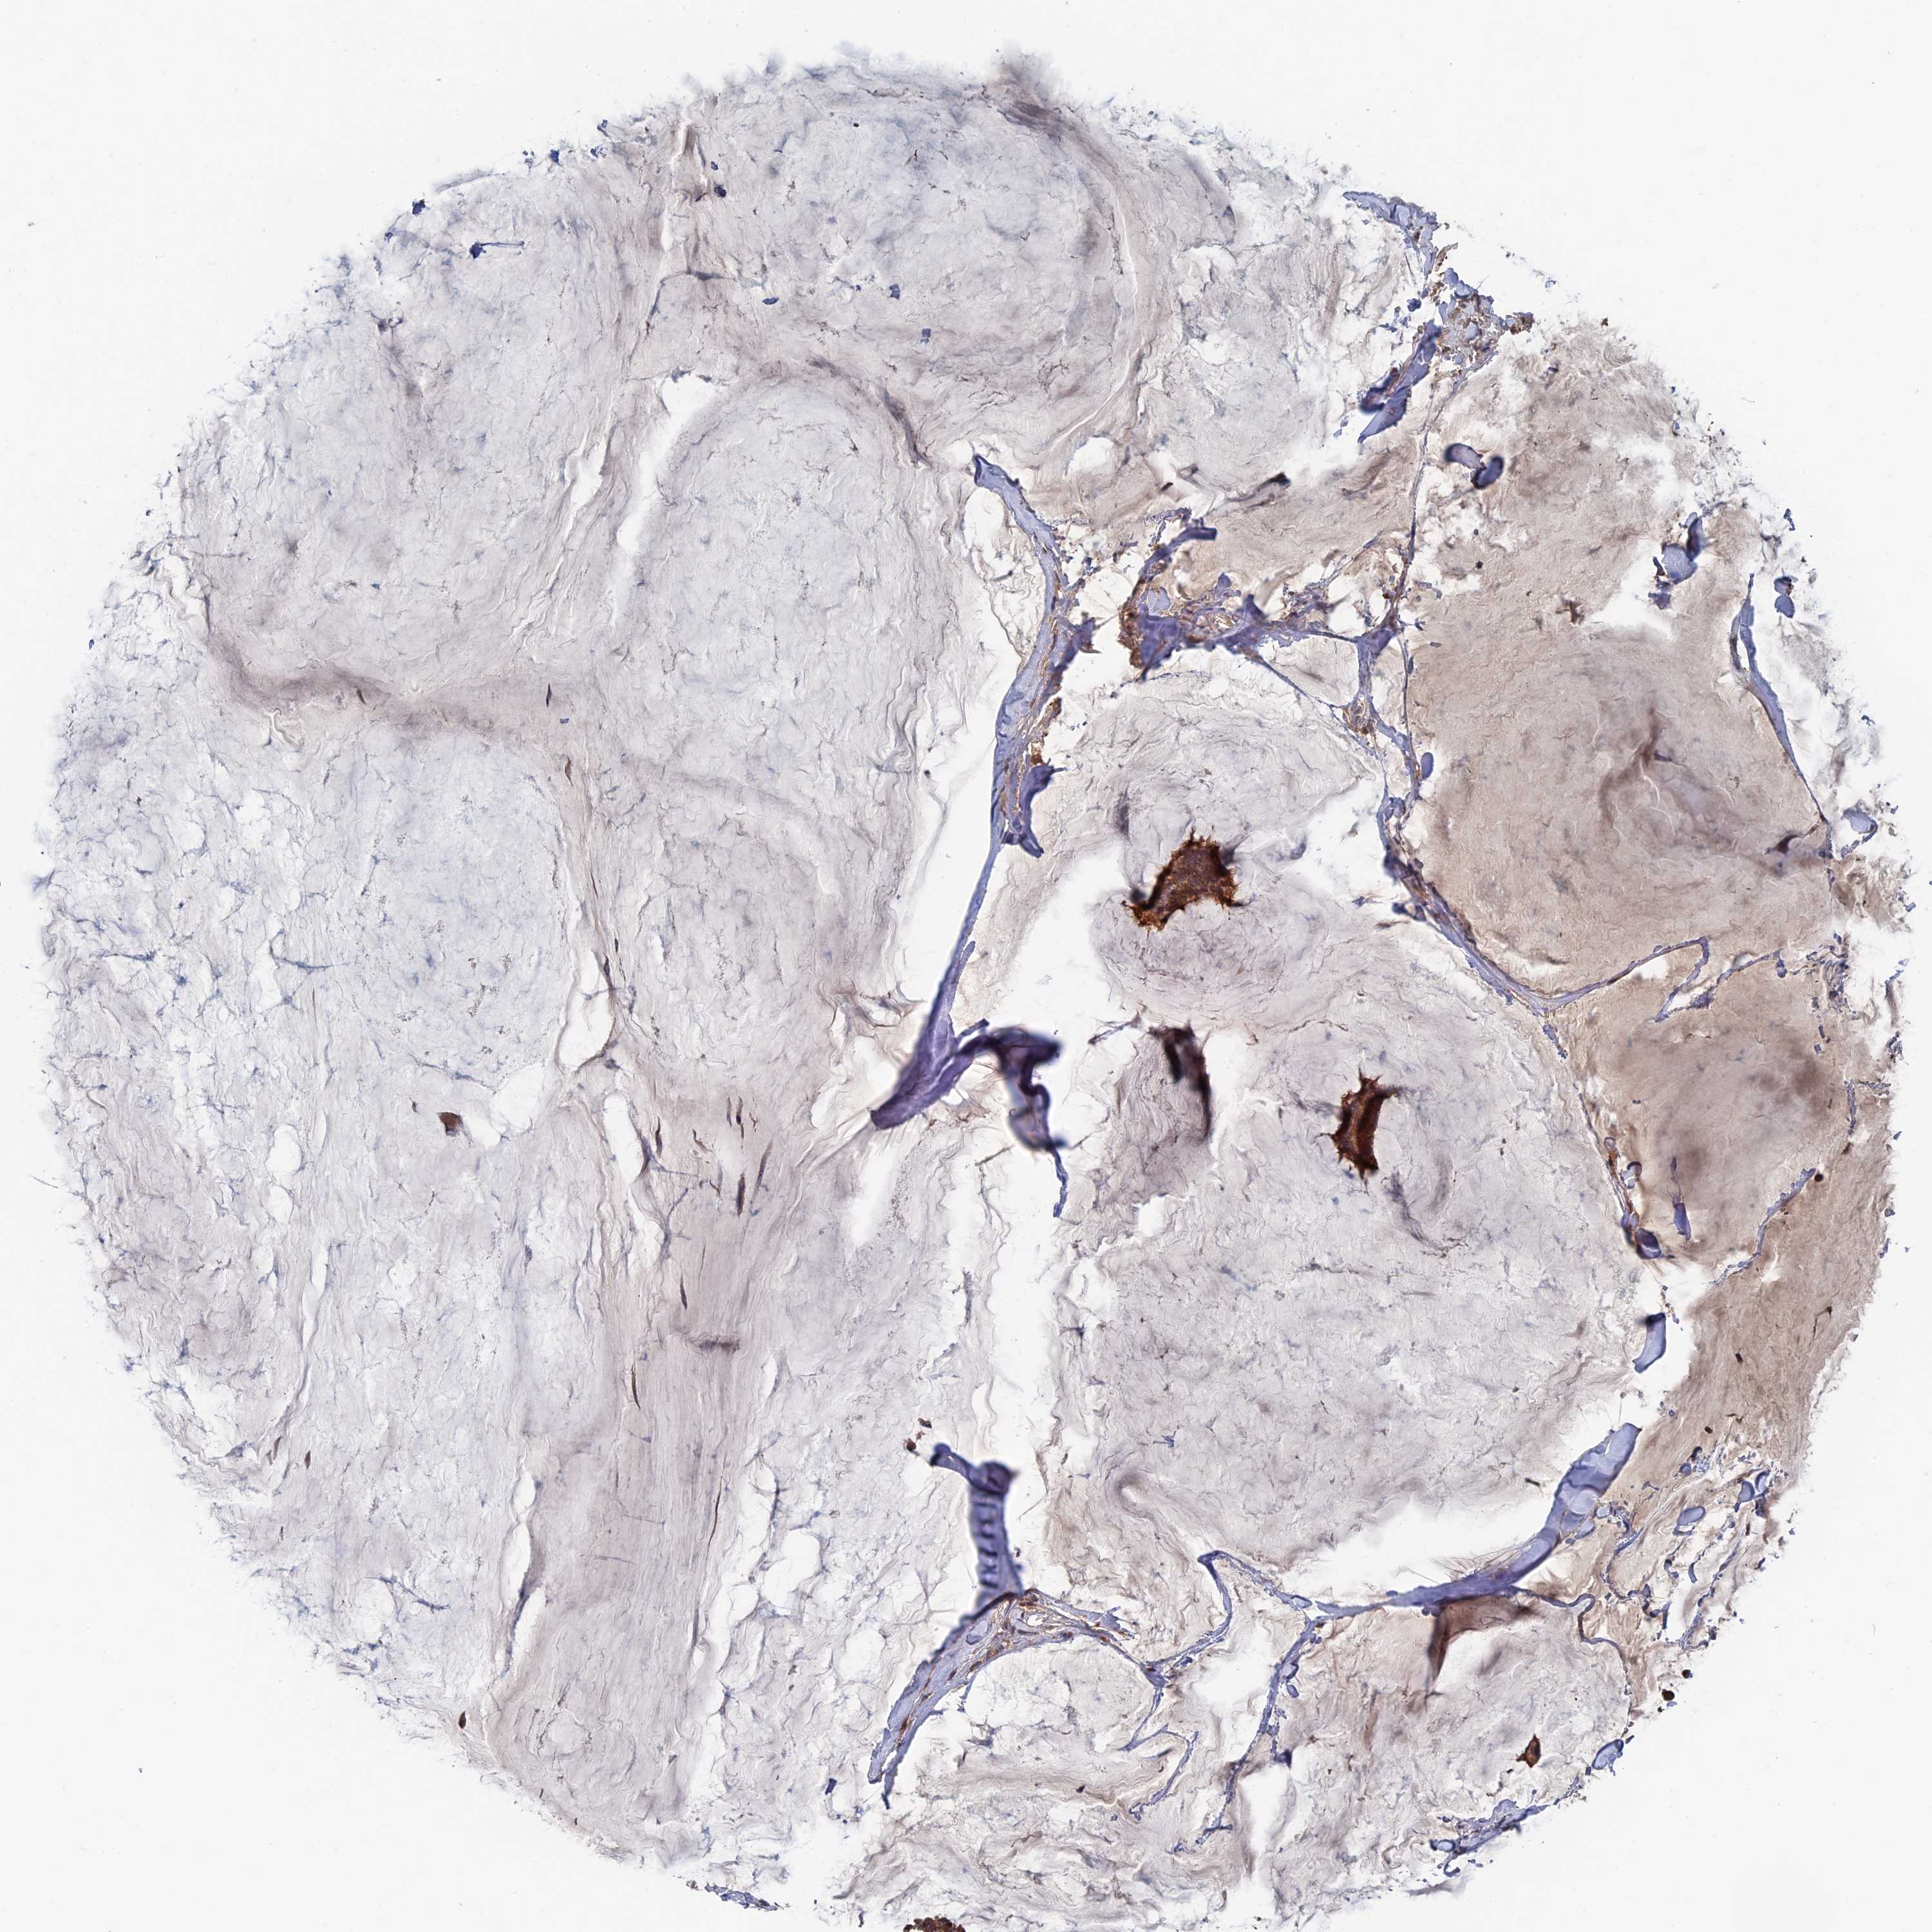

BRCA TCGA BRCA VALIDATION PROTEIN EXPRESSION